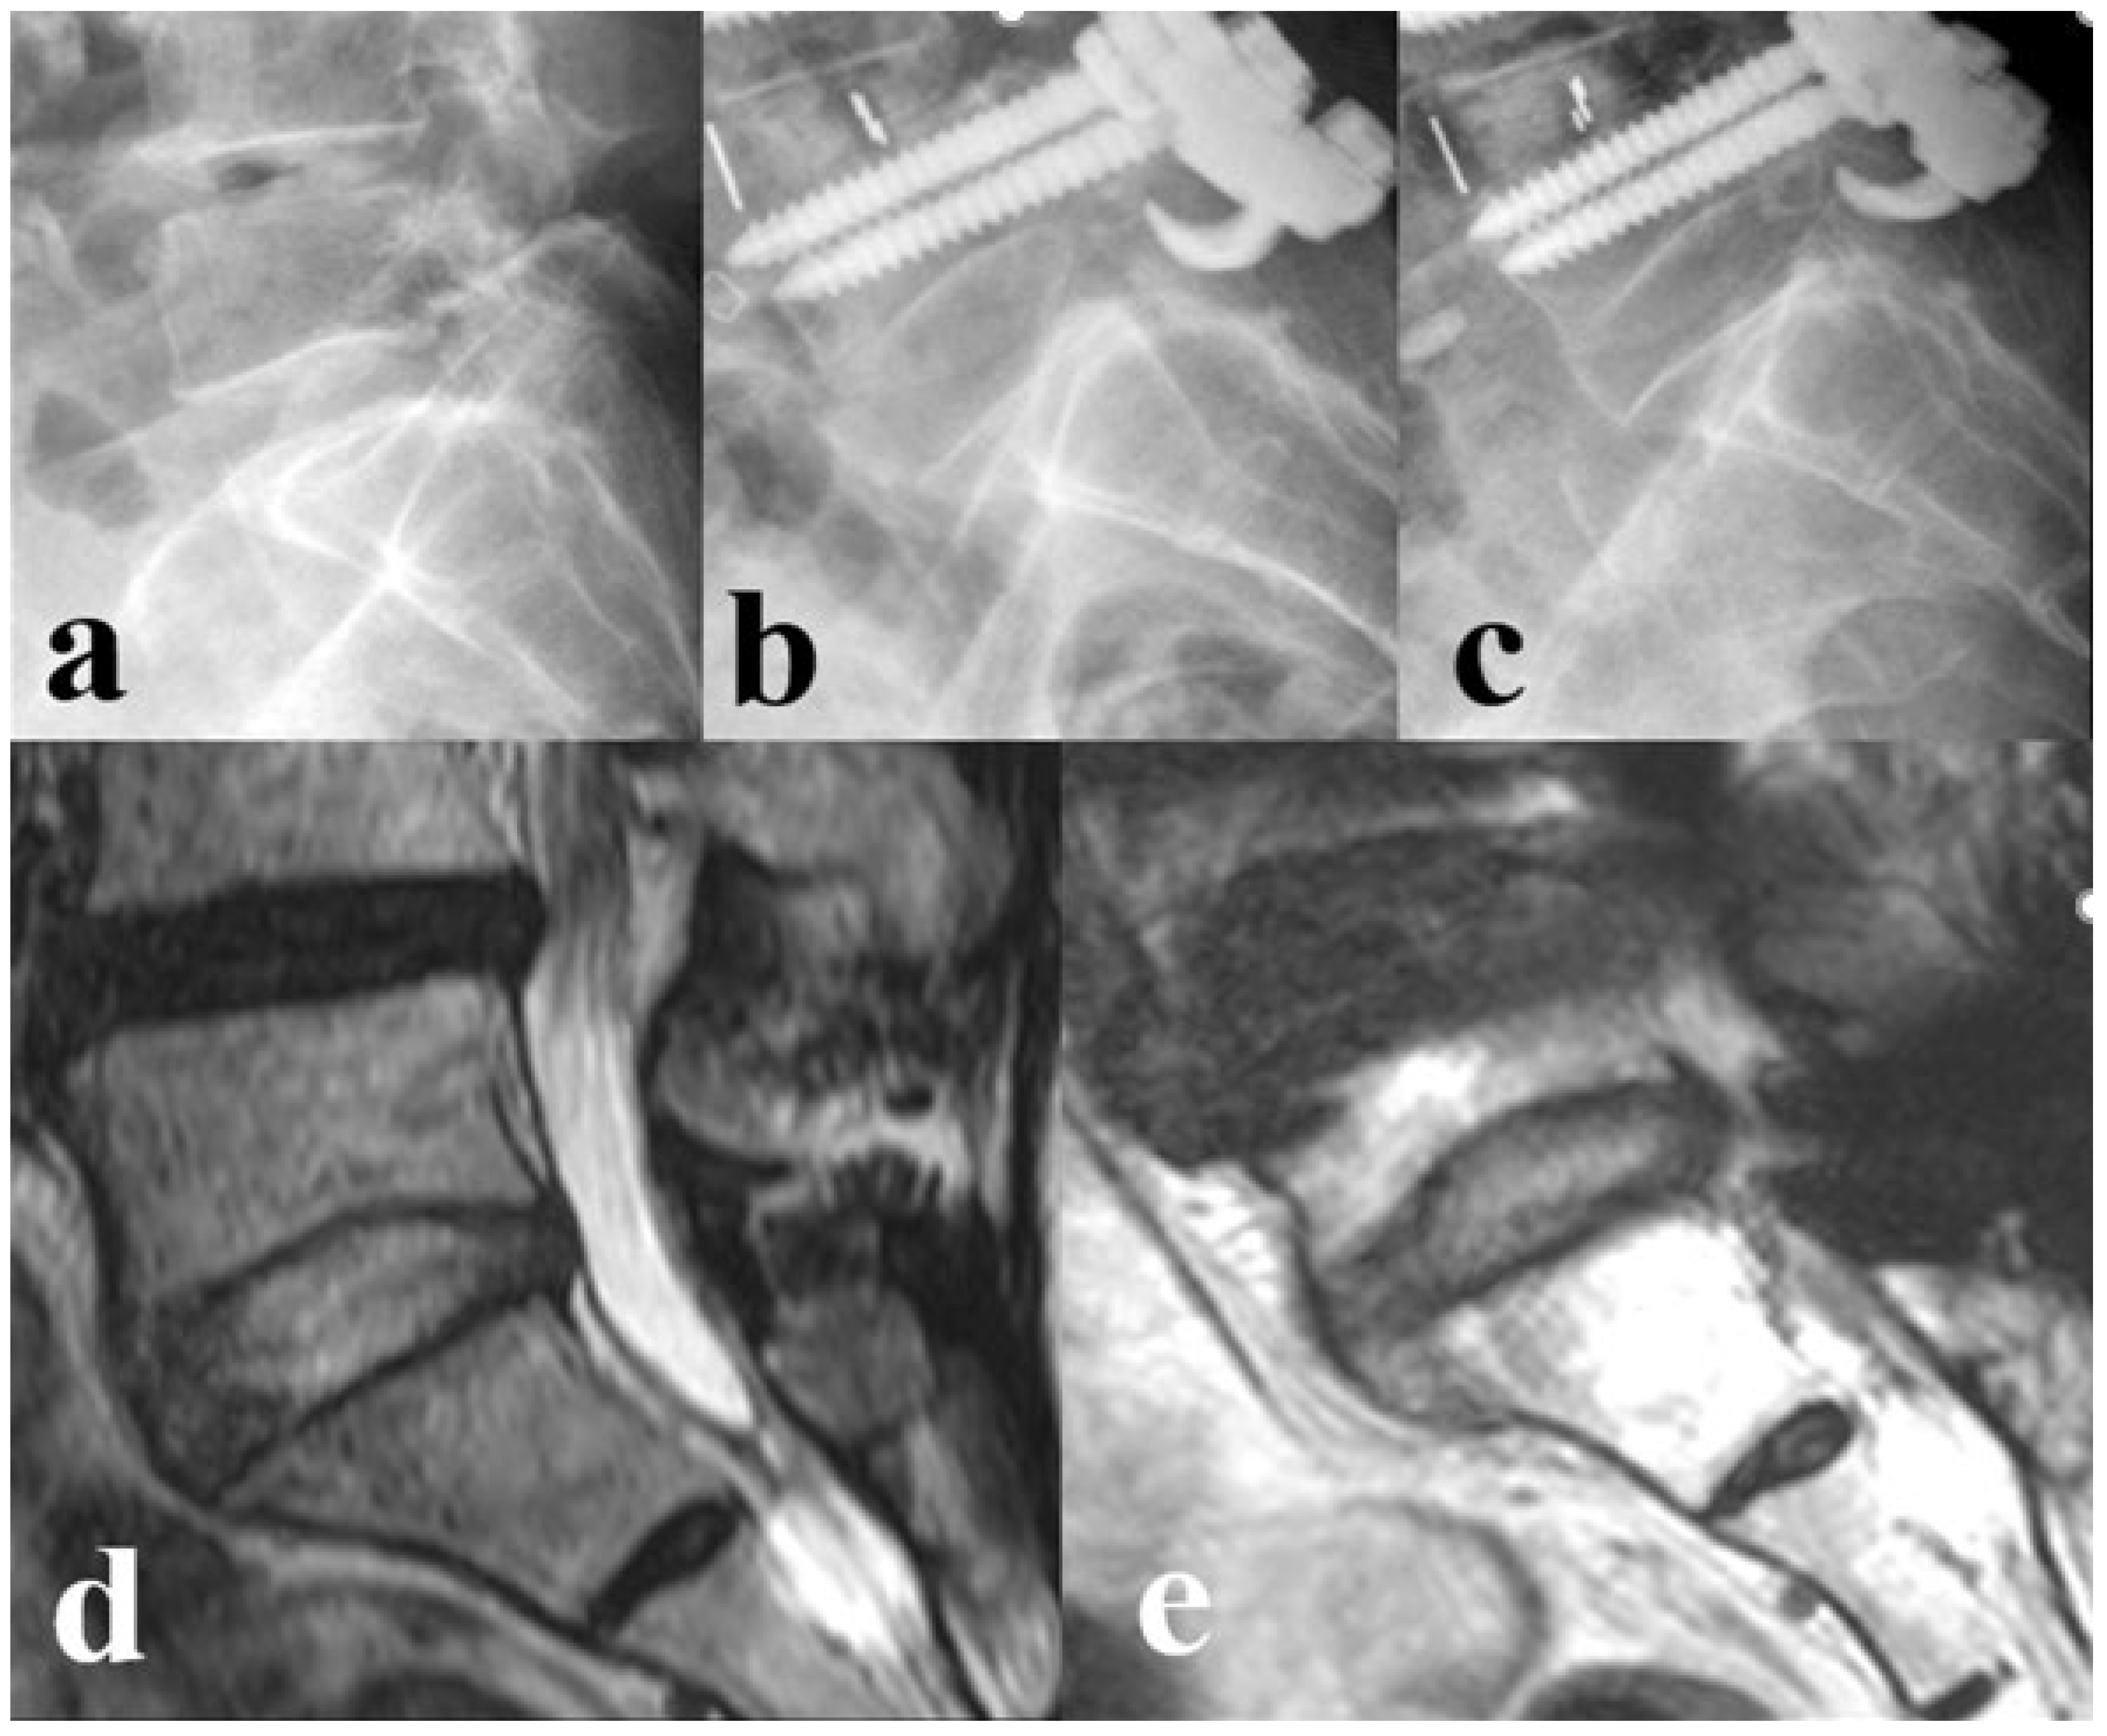

| Degeneration Grade of L5–S1 (n, %) | |||

| Preoperative | 1.000 | ||

| Pfirrmann grade 1, 2 or 3 (healthy) | 64 (100%) | 48 (100%) | |

| Pfirrmann grade 4 or 5 (degenerated) | 0 | 0 | |

| Follow-up at 2 years | <0.001 * | ||

| Pfirrmann grade 1, 2 or 3 (healthy) | 50 (78.1%) | 12 (25.0%) | |

| Pfirrmann grade 4 or 5 (degenerated) | 14 (21.9%) | 36 (75.0%) |